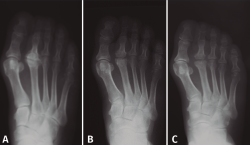

Las necrosis asépticas aparecen en aquellos puntos de nuestro aparato locomotor sometidos a importantes solicitaciones mecánicas, sea por microtraumatismos o por sobrecarga estructural. En el caso de la enfermedad de Freiberg, diversos autores(2,10,11,12) apoyan esta teoría que nosotros compartimos, ya que hemos visto muchos casos de afectación del segundo metatarsiano acompañando una insuficiencia del primer radio, sea por un hallux valgus o por un primer metatarsiano corto (Figura 2). En nuestro estudio a largo plazo sobre la enfermedad de Freiberg(13), sobre 16 pies operados, 12 padecían la sobrecarga mecánica.

Figura 2. Etiología mecánica. La enfermedad de Freiberg se asocia frecuentemente a una insuficiencia del primer radio.